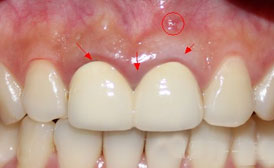

贝臣牙周治疗案例对比图